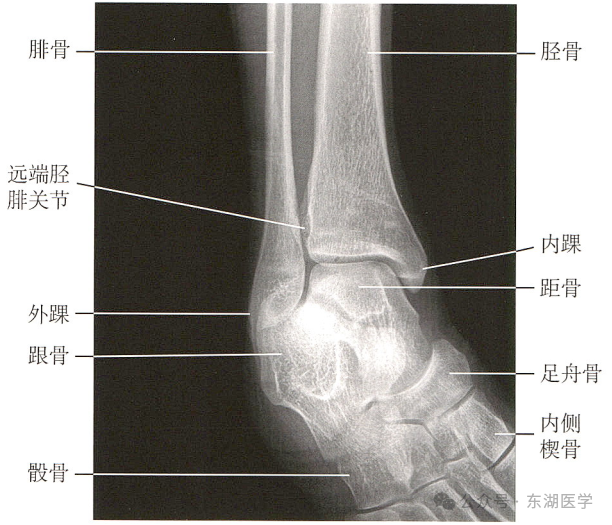

足以骨骼为支架,包括7块跗骨、5块跖骨、14块趾骨,彼此间借关节和韧带相连接。